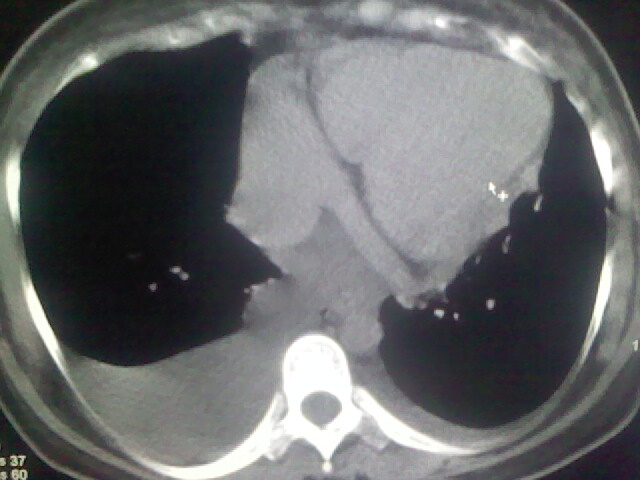

女,24,剖腹产后,突觉胸痛,干咳,不能平卧

胸水 感染 心影增大 肺水肿?

双肺“肺泡性肺水肿” “胸腔积液”!

双侧胸腔积液,肺泡性肺水肿。后纵隔好像有占位。

肝脾大,双侧胸腔积液,双肺水肿,肺动脉[包括远端小动脉],左右心房,左心室增宽,右心室主动脉无明显改变,符合左心功能不全征;;建议除外二尖瓣关闭不全,扩张性心肌病